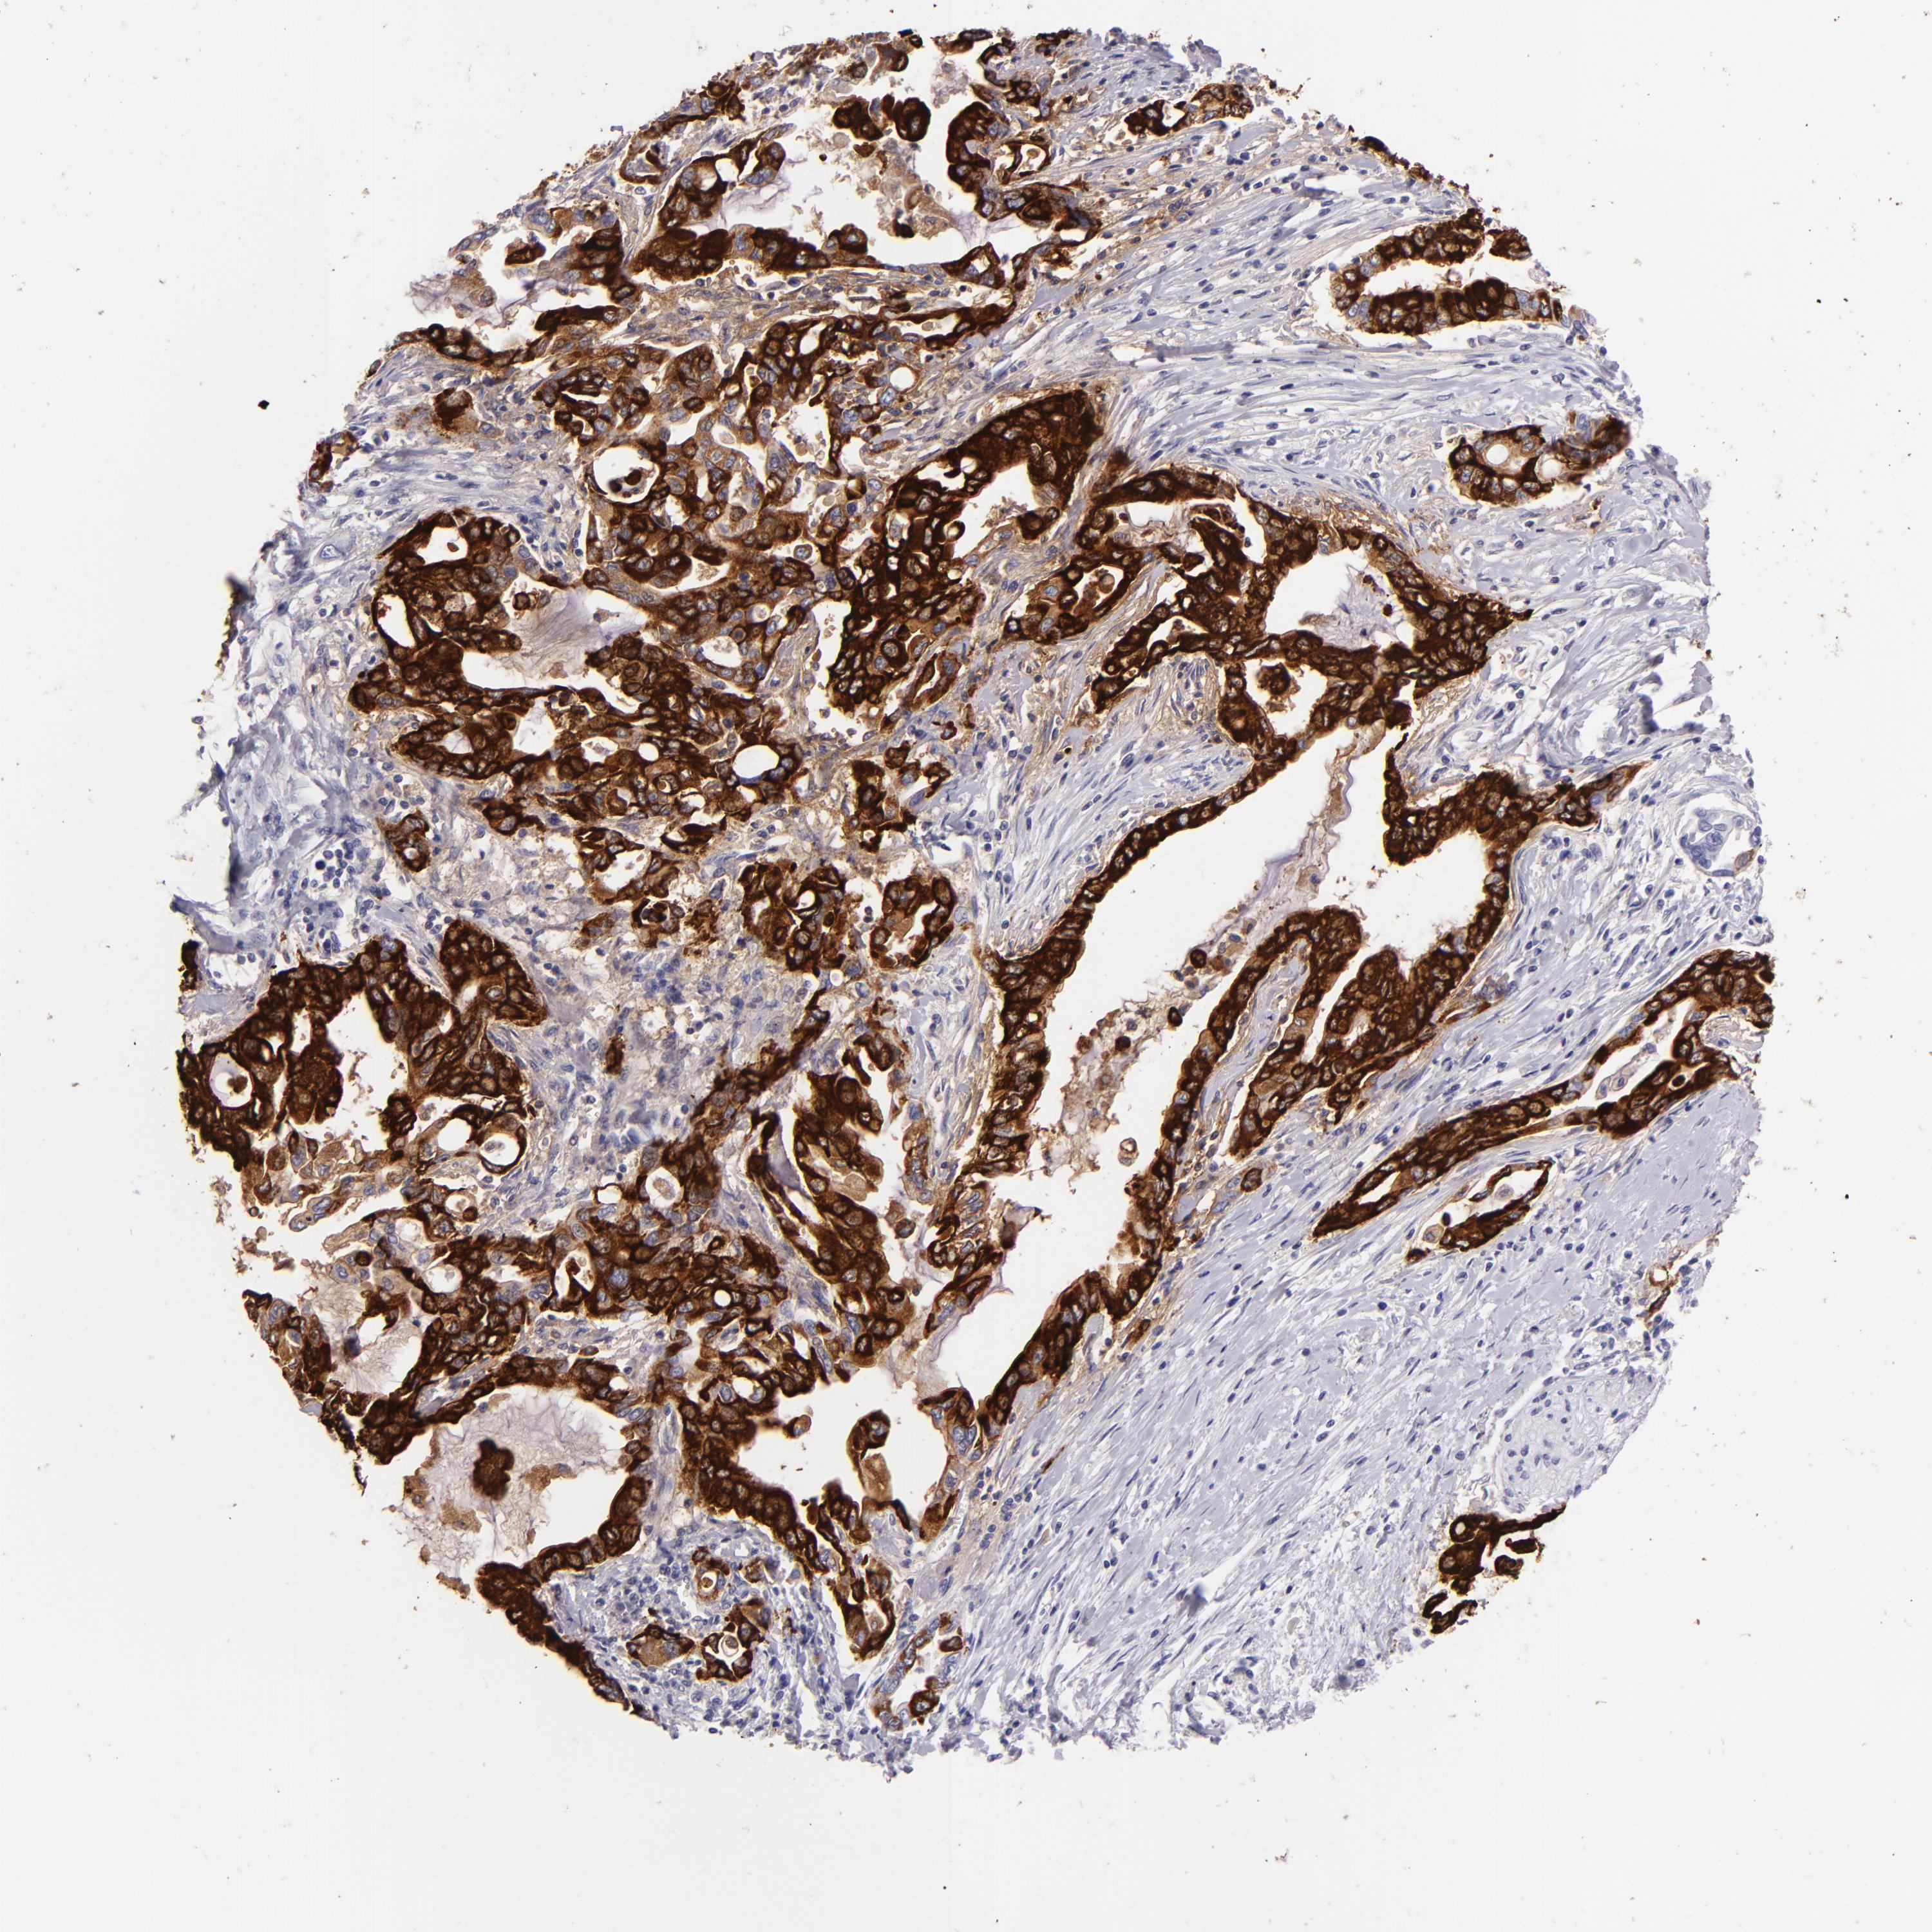

PANCREATIC CANCER - Protein expressioni

A mouse-over function shows sample information and annotation data. Click on an image to view it in a full screen mode. Samples can be filtered based on level of antibody staining by selecting one or several of the following categories: high, medium, low and not detected. The assay and annotation is described here.

Note that samples used for immunohistochemistry by the Human Protein Atlas do not correspond to samples in the TCGA dataset.

Antibody stainingi

Antibody staining in the annotated cell types in the current human tissue is reported as not detected, low, medium, or high, based on conventional immunohistochemistry profiling in selected tissues. This score is based on the combination of the staining intensity and fraction of stained cells.

Each image is clickable and will lead to virtual microscopy that enables deeper exploration of all samples and also displays staining intensity scores, fraction scores and subcellular localization as well as patient and tissue information for each sample.

HPA040615

HPA070378

HPA077637

CAB002774

CAB009395

Staining

High

Medium

Low

Not detected

Intensity

Strong

Moderate

Weak

Negative

Quantity

>75%

75%-25%

<25%

None

Location

Nuclear

Cytoplasmic/membranous

Cytoplasmic/membranous,nuclear

Adenocarcinoma, NOS

Adenocarcinoma, metastatic, NOS